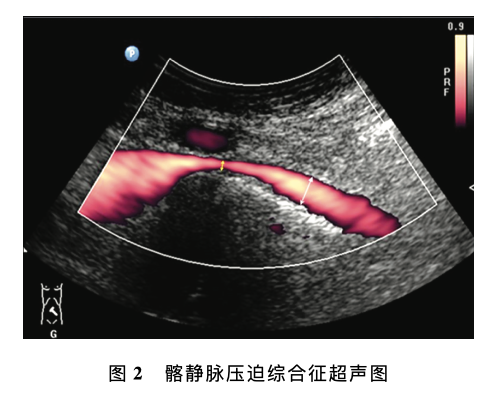

意见一:下肢静脉反流超声检查的推荐体位推荐体位为头高脚低位 (建议使用电动检查床), 即检查床头侧高于足侧,与地面夹角约30。条件有限的情况下可选择站立位或坐位,不推荐俯卧位评价下肢静脉反流。意见二:Valsalva (乏氏动作)的适用性乏氏动作主要用于评估隐-股静脉瓣、股静脉近 端静脉瓣的功能,不适于下肢远端静脉反流......